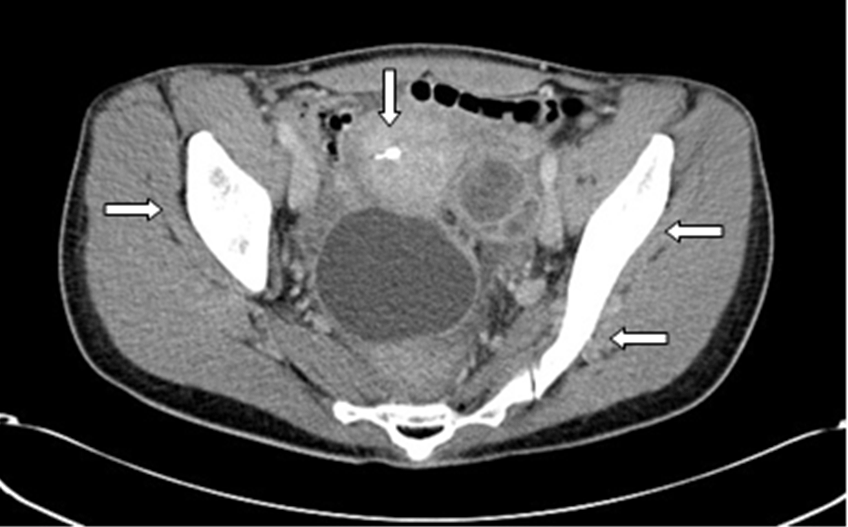

The patient was started on a regime of intravenous amoxicillin (1 gram tid for 6 weeks) followed by oral amoxicillin 1 gram tid for six months. She responded well to amoxicillin and gradually symptoms abated. After six weeks of antibiotic therapy, follow-up CT scan revealed two small fluid collections, which were most likely post-operative and did not warrant drainage. Further notable improvement was noted at sixth-month follow-up visit via computed tomography scan (Figure 4) and (Figure 5).

Figure 4: Axial computed tomography imaging of patient, six months into treatment. Lack of ovarian masses and free fluid in pelvis.